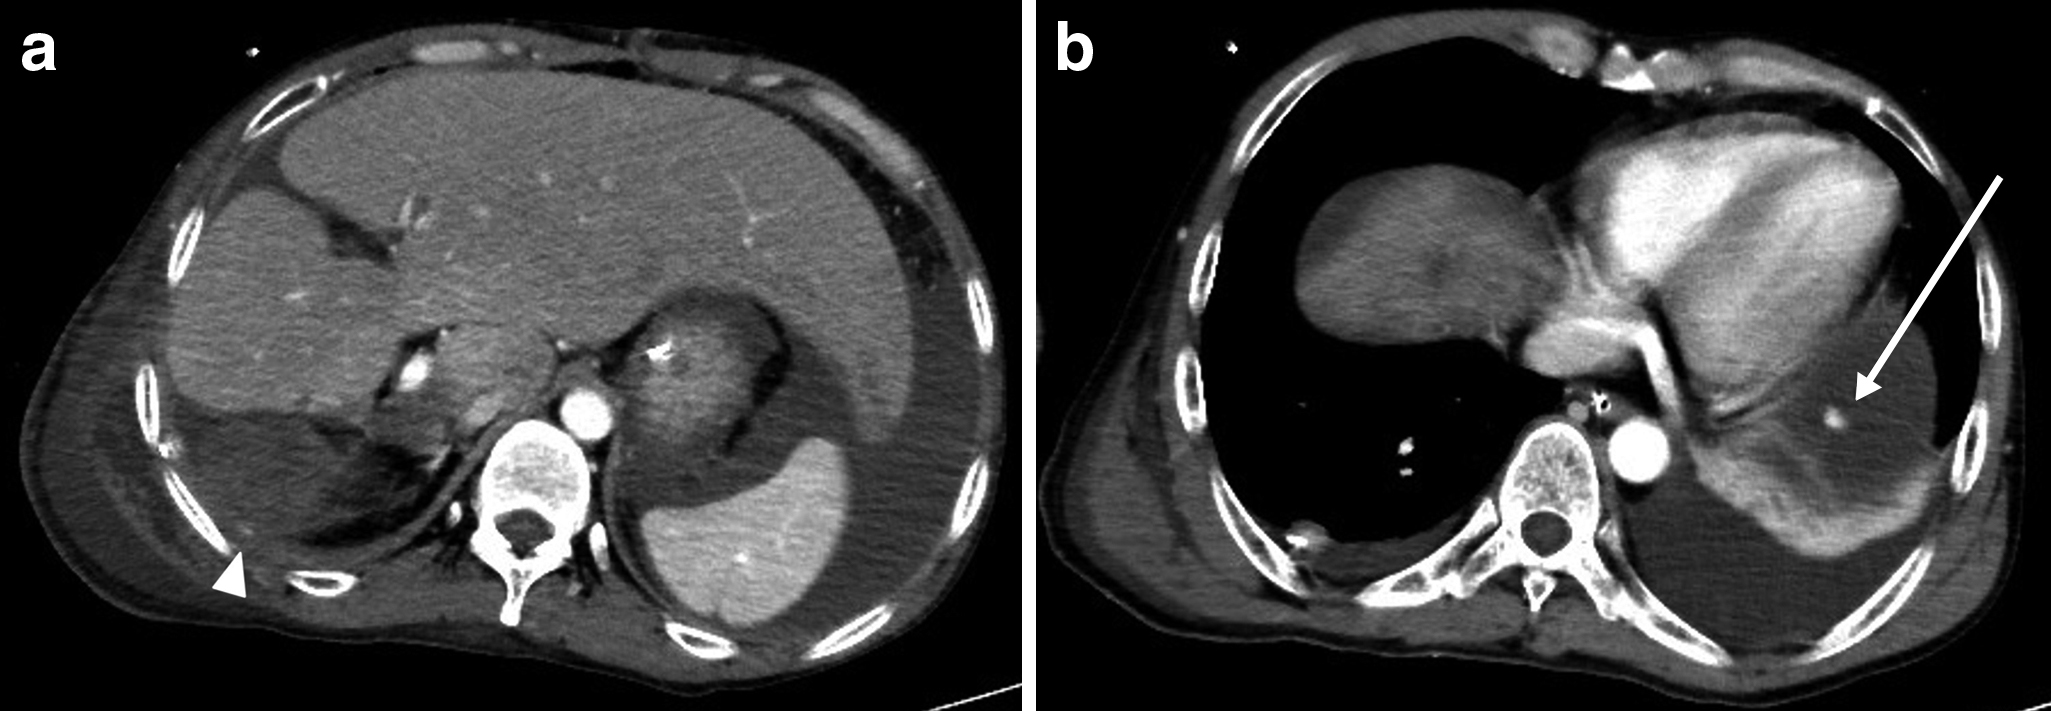

血管造影検査所見:右下横隔動脈からの出血を認め,塞栓術を施行した(Fig. 5).左下横隔動脈からの出血は認めなかったが,血管の攣縮による一時的な止血であり,再出血の可能性が高いと判断し,翌日に左も塞栓術を施行した.

Angiography shows extravasation of the contrast agent from the right inferior phrenic artery (arrow).